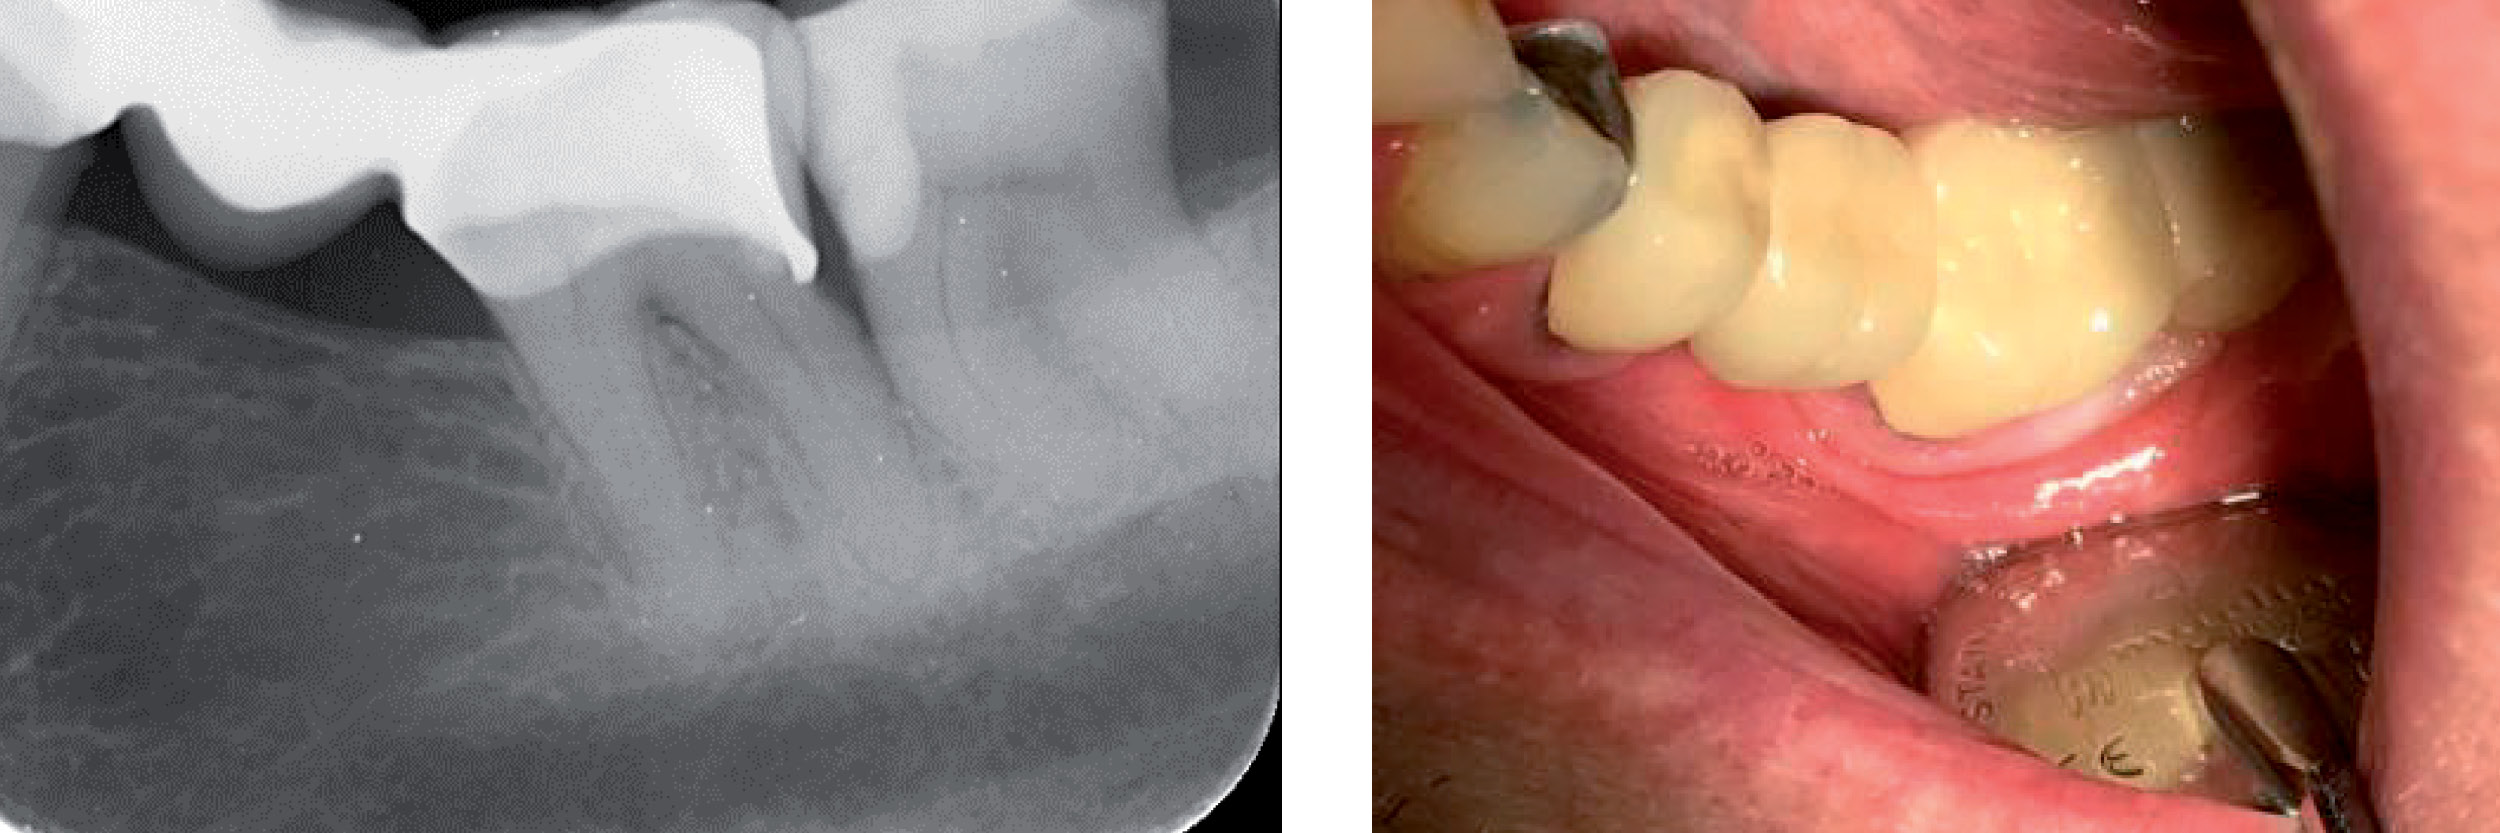

Fig. 4 Etter polering og EQUIA coat

Som en siste finish legges et tynt lag Equia Coat på fyllingsoverflaten, i henhold til bruksanvisningen, og lysherdes i 20 sekunder. Dette gjør fyllingen mer slitesterk, samt gir også samtidig mer glatthet og estetikk til fyllingen. (Fig.4) Kontaktpunktet mot 37 kontrolleres med tanntråd, med et godt resultat.

Fig. 5 Bitewing etter behandlingen

Fyllingsprosedyren var enkel og røntgen viser i etterkant en virkelig god form og adaptasjon. (Fig.5) Fyllingen kan se meget lys ut på bildene, men passer fint i fargen til den nysementerte broen.

Fig. 6 Bitewings etter 19mnd / Fig. 7. 19 mnd kontroll

Kontroll etter 19 måneder, legg merke til den gode røntgenkontrasten og kontaktpunktet er fortsatt optimalt, og fargen passer fint inn i omgivelsene. (Fig. 6 og Fig.7)